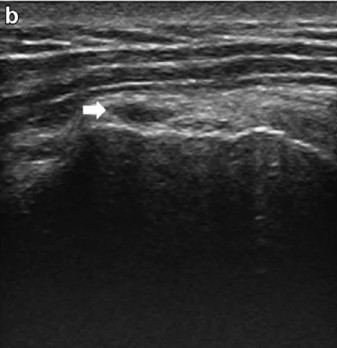

La anisotropía ocurre cuando el haz de ultrasonidos no incide de forma perpendicular sobre las fibras del tendón. En esa situación, el eco de retorno no llega correctamente al transductor, y la zona en cuestión aparece hipoecoica en la pantalla, es decir, oscura, como si hubiera una lesión.

En la zona de inserción tendinosa sobre el troquíter. La curvatura del tendón en ese punto hace que las fibras más profundas cambien de ángulo respecto al haz y generen una imagen hipoecoica que puede parecer una rotura parcial profunda.

El signo principal de una rotura parcial es un defecto focal hipoecoico en el espesor del tendón. A diferencia de la anisotropía, este defecto:

- Persiste al corregir el ángulo de incidencia.

- Tiene márgenes definidos y cierta morfología reproducible (normalmente fusiforme o triangular).

- Se localiza de forma consistente en los dos planos de exploración (longitudinal y transversal).